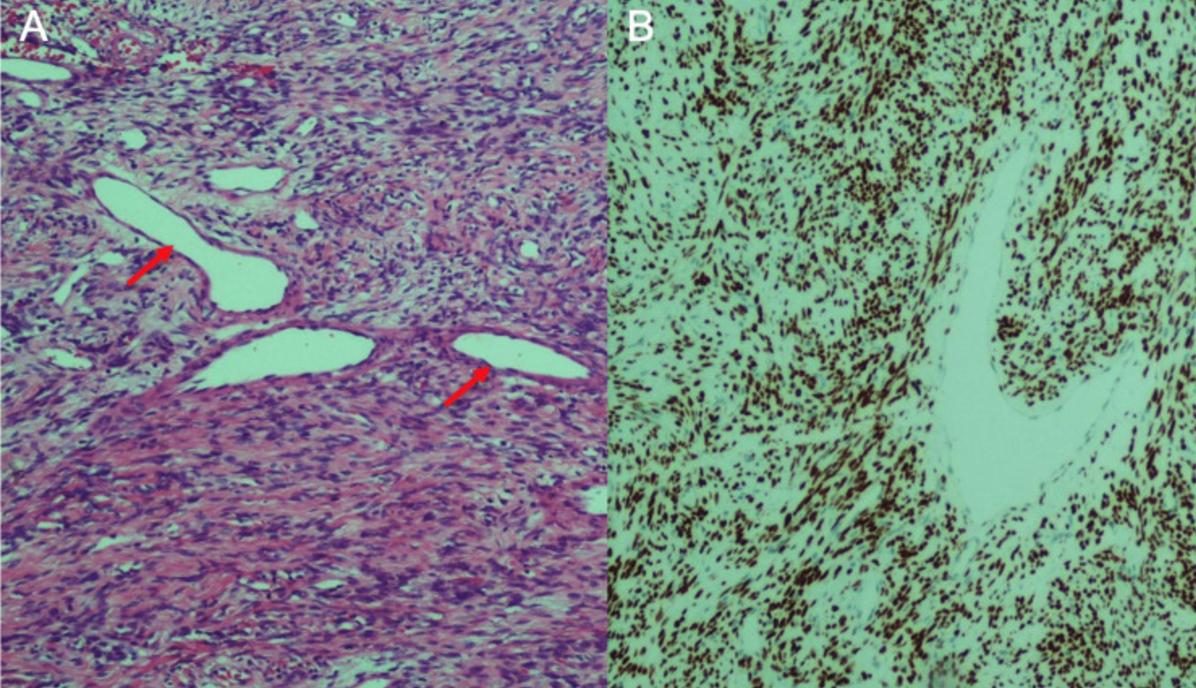

患者男性,24岁,两个月内进行性右侧鼻塞伴鼻漏,不伴鼻出血、面部疼痛或面部肿胀等不适。否认既往史及手术史。鼻内镜检查提示右鼻腔被一不规则肿物占位。中鼻甲被肿物遮挡,无法窥清(图1)。对鼻腔肿物进行了活检。

图1